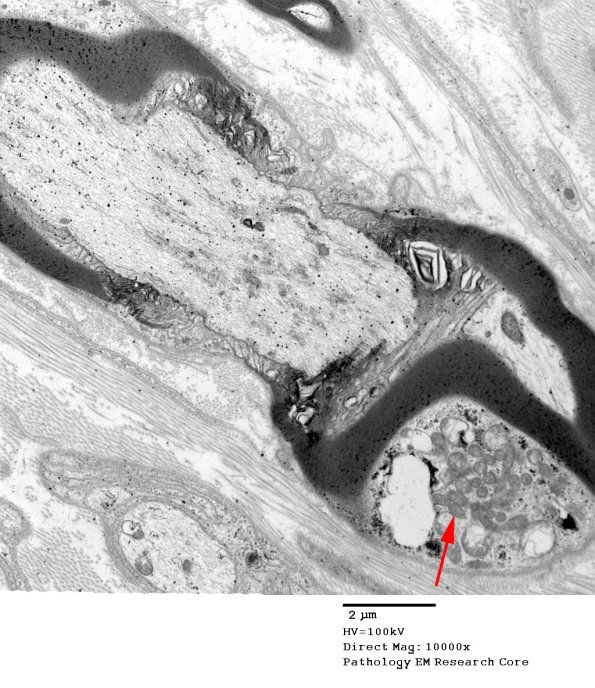

12A 1-5 Multiple nodes from a patient in which the tissue was well preserved and oriented. (electron micrographs) ---- 12A1 A collection of mitochondria in the paranode (arrow) in the longitudinal section of this node. (electron micrograph)